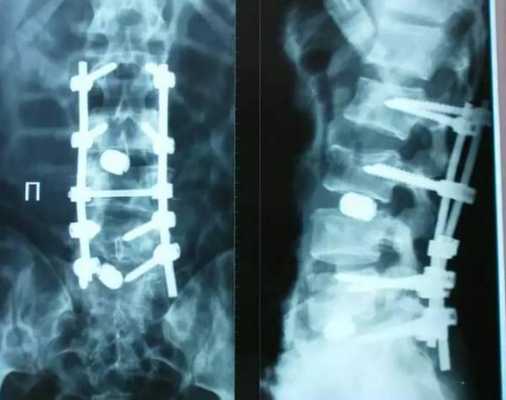

Рентген послеоперационной перкутанной ТПФ у пациентки с множественными переломами позвоночника